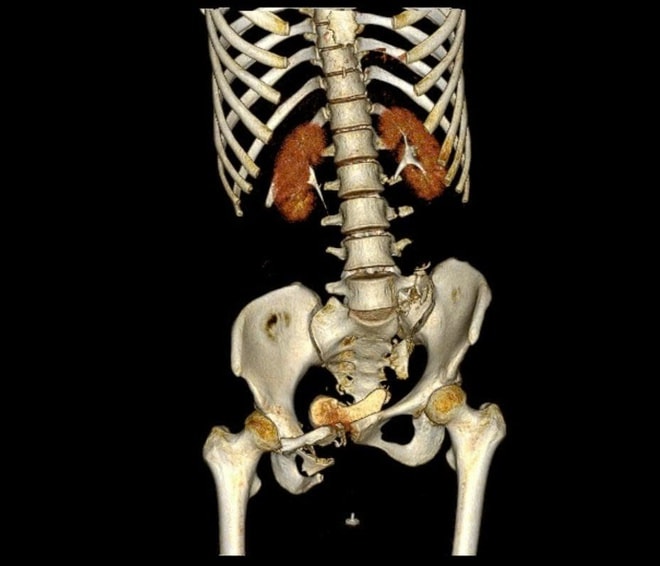

BS.CKI Trần Quang Khanh - Khoa Phẫu thuật chi dưới, Viện Chấn thương Chỉnh hình, Bệnh viện Quân y 175 cho biết: "Bệnh nhân bị gãy khung chậu kiểu 'gió thổi' (Windswept pelvic ring fracture) – một dạng gãy rất phức tạp, chiếm khoảng 6% các trường hợp gãy khung chậu. Đây là loại gãy do chấn thương năng lượng cao, kết hợp giữa lực nén trước - sau và lực tác động bên, khiến một bên cánh chậu mở ra, bên còn lại khép lại, tạo hình ảnh đặc trưng như 'bị gió thổi'. Thường tổn thương còn đi kèm gãy xương cùng và tổn thương khớp mu, làm mất vững toàn bộ vòng chậu, gây nguy hiểm tính mạng nếu không được xử trí đúng cách".

Khung xương chậu bệnh nhân trước và sau phẫu thuật. Ảnh: BVCC.